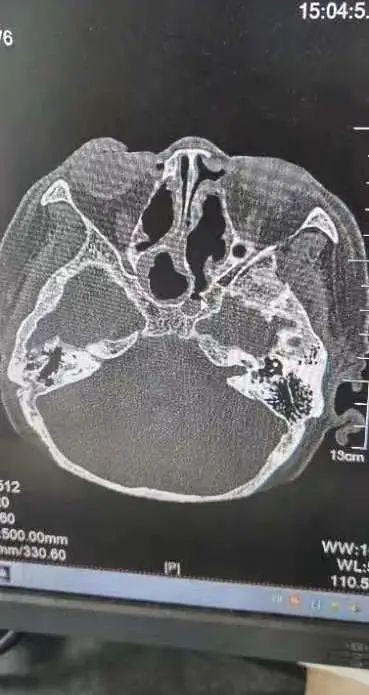

術(shù)前術(shù)后CT對(duì)比

“由于蝶竇位置特殊,位居顱底深部,與垂體、頸內(nèi)動(dòng)脈、視神經(jīng)等重要結(jié)構(gòu)緊密相連,一旦損傷頸內(nèi)動(dòng)脈,將導(dǎo)致大出血,損傷視神經(jīng)則可能造成不可逆的失明。其次,這個(gè)病例具有迷惑性,膿囊腫壓迫的是右側(cè)蝶竇,正常來說是右眼無光感,但實(shí)際上是左側(cè)視力失明,鼻竇CT雖然能看到占位,但是看不到蝶竇膿囊腫侵蝕破壞的地方。”王浩臨危不亂,在鼻內(nèi)鏡下精細(xì)操作,探查發(fā)現(xiàn),由于右側(cè)巨大腫物擊穿蝶竇間隔進(jìn)而造成左側(cè)視神經(jīng)管受損而導(dǎo)致左眼失明,手術(shù)全程順利,術(shù)后予以抗感染、止血等治療,岳老太頭痛等癥狀消失,左眼復(fù)明。一周后出院時(shí)向耳鼻喉科醫(yī)護(hù)人員豎起了大拇指,為他們精湛的醫(yī)術(shù)與貼心的護(hù)理服務(wù)點(diǎn)贊。